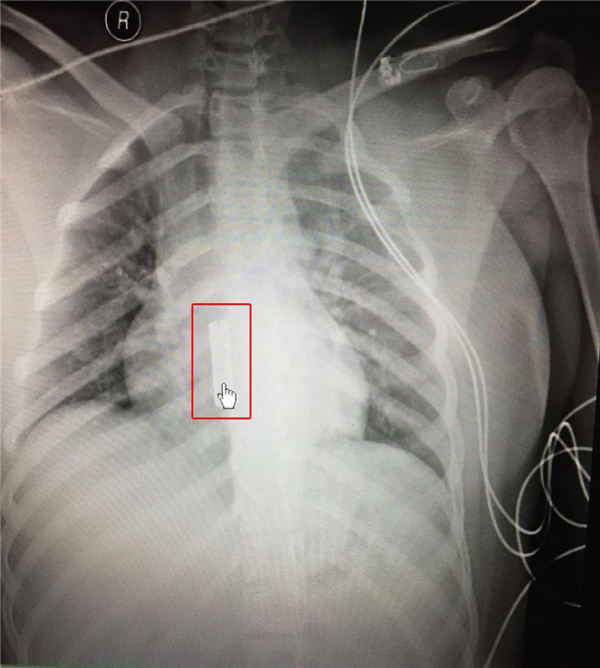

经放射科做床透胸片后,发现患者食道内还有异物,急诊医护人员又迅速联系了消化科、普外科前来会诊,经进一步检查讨论,决定由消化科通过胃镜将异物取出。

经联系,消化科殷军社医生和胃镜室工作人员紧急返院手术,医护通力协作,小心操作,终于成功将食管内的异物取出。之后,鉴于安全考虑,将女孩儿转入ICU密切观察治疗,随后女孩意识逐渐清醒,脱离了危险。

经查,异物是一个长约4厘米、直径约1厘米的管状金属物。